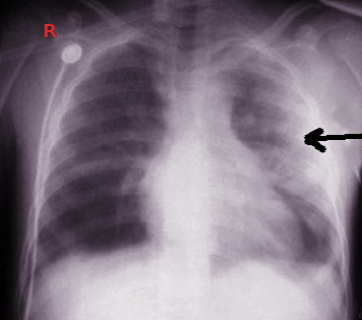

13) Liver transplant 2 months ago + SOB + fever + dullness to percussion of chest with this imaging finding = EMPYEMA After liver txp, you can get recurrent pleural effusions from inflam around R hemidiaphragm --> immunocompromised + bacteria = empyema Tx: chest tube + abx